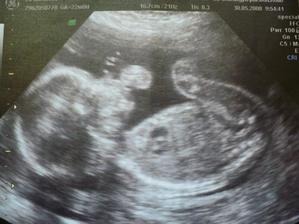

17. kvě 2008

Mimísek

Tak už to víme na 99%, že to bude kluk! A tak začínám pořizovat výbavičku a všechno si to moc užívám...